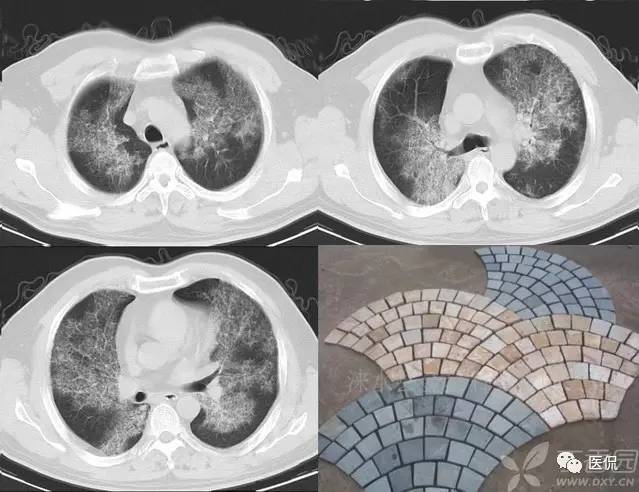

碎石路征

碎石路征或称铺路石征,是胸部CT上的一种影像学征象,主要表现为在弥漫性或散在分布的毛玻璃样浸润影中,有小叶间隔增厚、小叶内线状影重叠存在。碎石路征最初在肺泡蛋白沉积症(PAP)的病例中发现,并认为是PAP特征性的胸部CT表现;但实际上,感染性疾病、肿瘤、特发性肺弥漫性疾病(DPLD)、吸人性病变等都也可以出现。

1)PAP是一种罕见病。各个年龄均可发病,以20~50岁的成年人多见。干咳、呼吸困难是其最常见的临床症状,而胸膜性胸痛、乏力、低热等则较少见。其胸部X光片表现是双侧对称性的肺泡实变或毛玻璃影,主要分布于肺门及肺门周围而类似肺水肿。CT的典型表现包括:①毛玻璃影及实变影与小叶间隔增厚交织形成碎石路征样改变;②在肺泡实变与正常的肺实质之间出现很明显的分界线,形成“地图样”分布。PAP碎石路征的组织学基础是:毛玻璃影及实变影与肺泡内充满PAS染色阳性、富含脂质的蛋白样物质有关;小叶间隔增厚影与肺泡壁因纤维组织增生或II型肺泡上皮细胞增生及淋巴细胞浸润有关。依据碎石路征和“地图样”分布,结合患者临床与影像学表现不平行的特点,是诊断PAP的诊断的不要依据。

典型的肺泡蛋白沉积症: